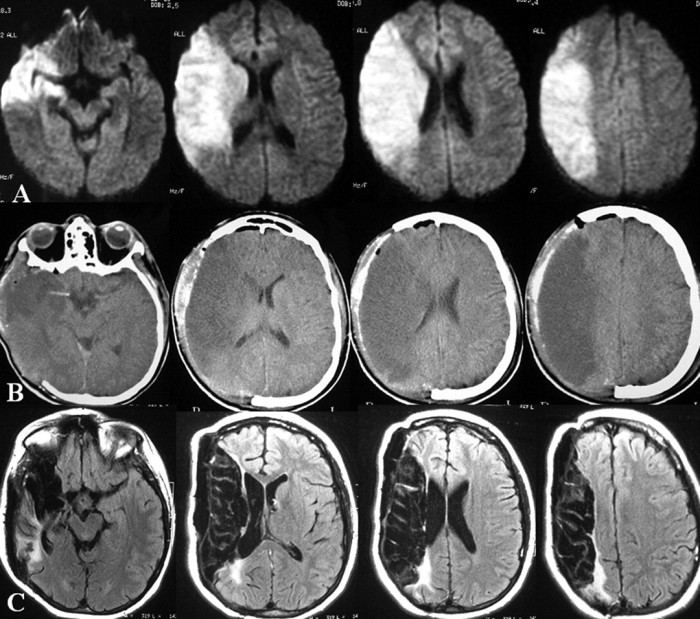

5 Craniectomy

A craniectomy is a very dangerous operation done in the brain. This operation needs that the portion of skull eliminated to reach the brain and it is not replaced when the surgery is done, to get the recovered patients with the danger of brain damage following the surgery. There are other risks like loss in the vision, mobility and memory.